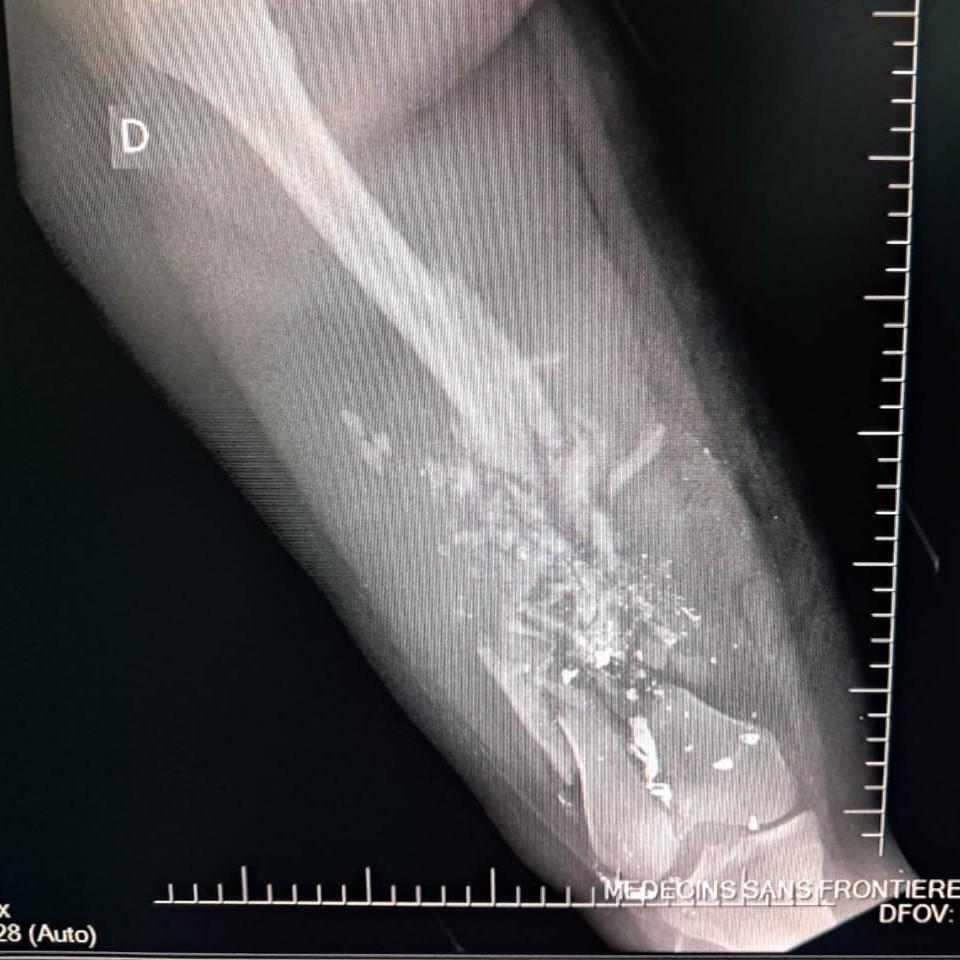

En los primeros seis meses de 2025, nuestros equipos atendieron a 2.600 supervivientes de violencia sexual, ingresaron a 13.300 pacientes en urgencias y trataron a 2.267 víctimas de violencia. De estas últimas, el 26 % eran menores de edad, frente al 11 % en 2024. La mayoría de los menores tenían menos de 15 años y un tercio eran niñas. En este periodo, uno de cada tres menores ingresados por lesiones relacionadas con la violencia sufría heridas de bala.

El 20 de septiembre, 17 heridos fueron atendidos en el hospital de MSF en Drouillard tras un ataque con drones llevado a cabo ese mismo día en el barrio de Cité Soleil. Entre estos pacientes se encontraban dos hombres que ya habían fallecido a su llegada, otro hombre que murió durante el traslado, diez mujeres —una de ellas murió de camino al Hospital de traumatología de MSF en Tabarre— y tres niños que, trágicamente, no sobrevivieron a sus heridas. Otras dos mujeres heridas en el mismo ataque fallecieron en el cercano Hospital materno Isaïe Jeanty, donde también trabajamos.

Esta violencia se produce en el contexto de un conflicto territorial en el que la población se encuentra expuesta en primera línea, atrapada entre la amenaza de los drones explosivos y la brutal violencia de los grupos armados que saquean y queman casas, destruyen barrios, aterrorizan a las comunidades y utilizan cada vez más la violencia sexual como arma de control, castigo y extorsión.